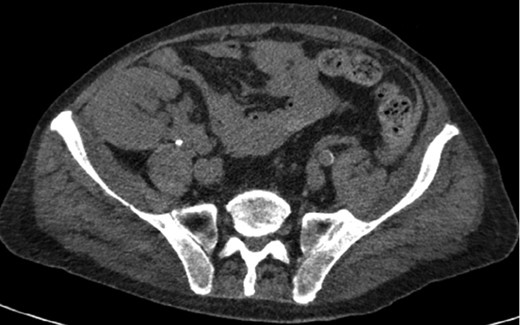

A 68-year-old male with history of living donor renal transplant presented to the ED with acute onset of profound weakness, fatigue, left upper quadrant abdominal pain, hypotension and lactic acidosis. On exam, he exhibited mild left upper quadrant and epigastric tenderness without evidence of peritonitis. CT imaging demonstrated splenomegaly with a large splenic hematoma measuring 15.7 × 9.2 × 12 cm and associated hemoperitoneum (Figs 1–3). In addition, innumerable osseous lytic lesions were identified. Given these findings, emergent surgical consultation was obtained and his coagulopathy reversed. He remained hypotensive despite resuscitation, thus was taken for laparotomy. Upon abdominal entry, a large amount of old clot was evacuated. The abdomen was packed in all quadrants in the standard fashion. Upon removal of the left upper quadrant packs, active hemorrhage began to well from the region of the spleen which was mobilized and removed via splenectomy. Upon gross inspection, the spleen was hyperemic and abnormally indurated, with an avulsion type injury extending several centimeters across the inferior pole. There was no evidence of pseudoaneurysm or other gross pathology. Given the patient was mildly hypothermic and coagulopathic with continued oozing from the retroperitoneum, the decision was made to pack the splenic fossa and place a temporary wound vac. The patient was transported to the ICU for resuscitation and brought back to the OR the next morning for re-exploration and closure. Despite hemodynamic stabilization, he underwent a prolonged hospitalization complicated by atrial fibrillation, renal allograft failure, VAP, and ultimately PEA arrest progressing to asystole. He died 6 weeks following splenectomy. The pathology from the spleen revealed splenomegaly with parenchyma that was replaced with amorphous and acellular eosinophilic material. Histologic staining (Thioflavin-T) was positive for amyloidosis, AL-type. Oncology was consulted based on these findings with concern for lymphoproliferative disorder given osseous findings on CT, splenic pathology, and history of immunosuppression. Bone marrow biopsy was subsequently obtained which showed more than 50% atypical plasma cells/plasma blasts (CD138+; PAX5 negative; EBV (EBER) negative) and no amyloidosis, consistent with multiple myeloma. Urine showed Bence-Jones protein. Serum immunofixation studies were remarkable for a monoclonal IgG lambda gammopathy, consistent with the diagnosis of AL amyloidosis associated with systemic myeloma.

Axial CT imaging of the pelvis demonstrating heterogeneous fluid (blood) in the pelvic small bowel mesentery. Also shown is the patient’s renal transplant with clear perinephric fat planes. The renal graft was grossly uninvolved and viable appearing at the time of laparotomy.